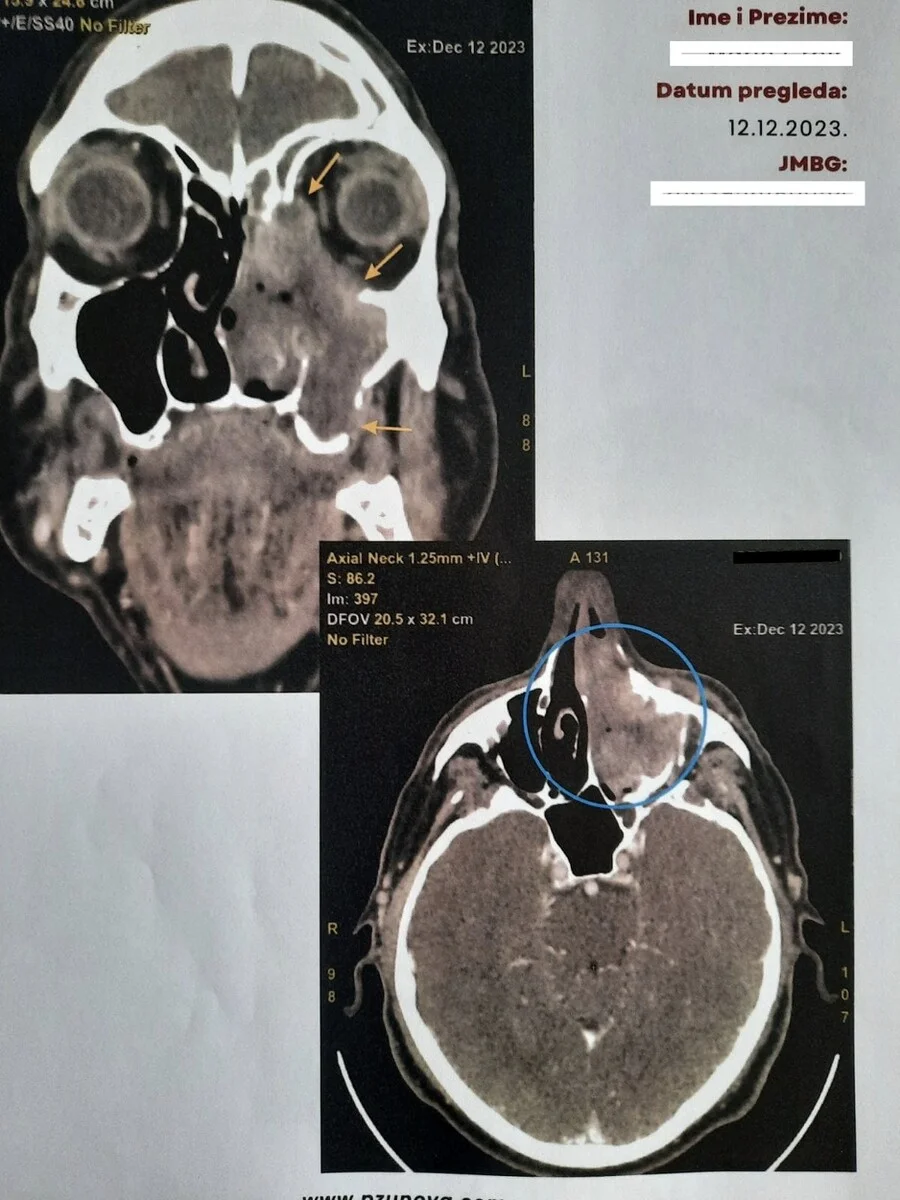

Nedim Leto je na čelu multidisciplinarnog tima, a u razgovoru za Klix.ba je kazao da se ove operacije izvode na teškim onkološkim pacijentima sa uznapredovanim karcinomima glave, lica i vrata.

Dodao je da pacijenti dobivaju kvalitetan tretman u ovoj ustanovi te da je osim uklanjanja tumora jako važna i rekonstrukcija defekta koja se radi lokalnim ili udaljenim režnjevima (deltopektoralni, pektorali, temporalnim mišićem) te slobodnim koštanim graftovima sa kriste ilijake i rebra.